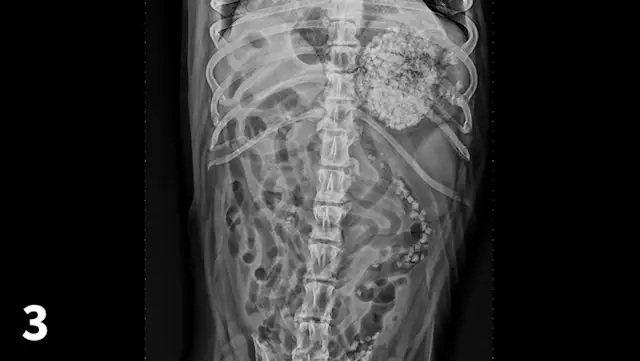

Abdominal radiographs, repeated 14 hours later, reveal minimal aboral movement of the mineral opacities (Figures 4 and 5; see below).